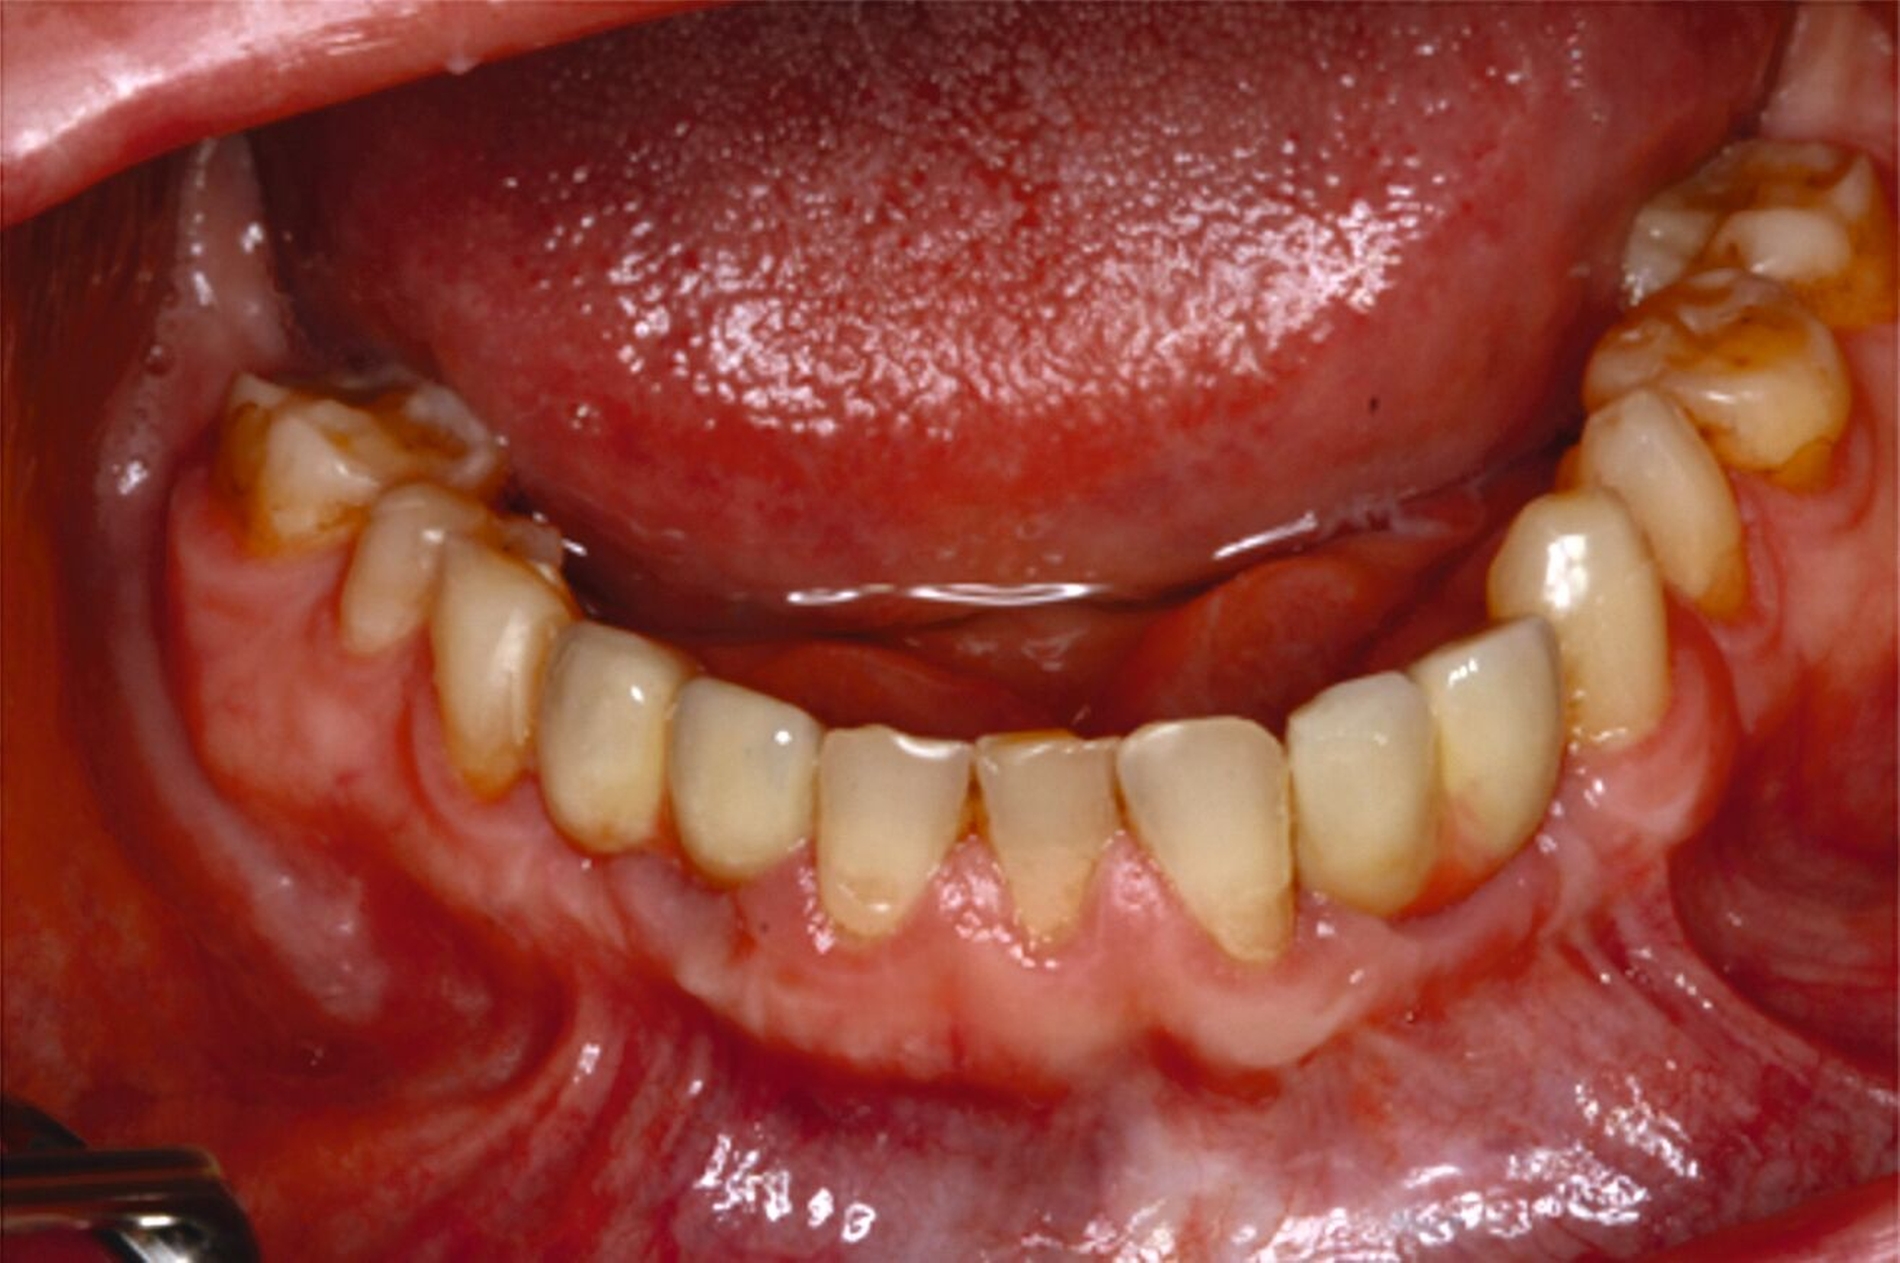

Eine mögliche und indizierte Umstellungsosteotomie wurde vom Patienten abgelehnt. Da seitens des Patienten eine Kopfbissstellung möglich war, wurde eine Bissumstellung und -hebung mit nur noch geringgradigem Vorbiss und anschließender Zahnimplantation in Erwägung gezogen. Begonnen wurde mit einer temporären Schienentherapie zur Neuorientierung der Bisslage (Abbildung 3). Da der Patient die angepasste Bisshebung tolerierte, wurde diese nach Entfernung der persistierenden Milchzähne 55, 53, 52, 62 und 83 temporär mittels einer Valplastprothese (Abbildung 4) als Interimsersatz im Oberkiefer gesichert.